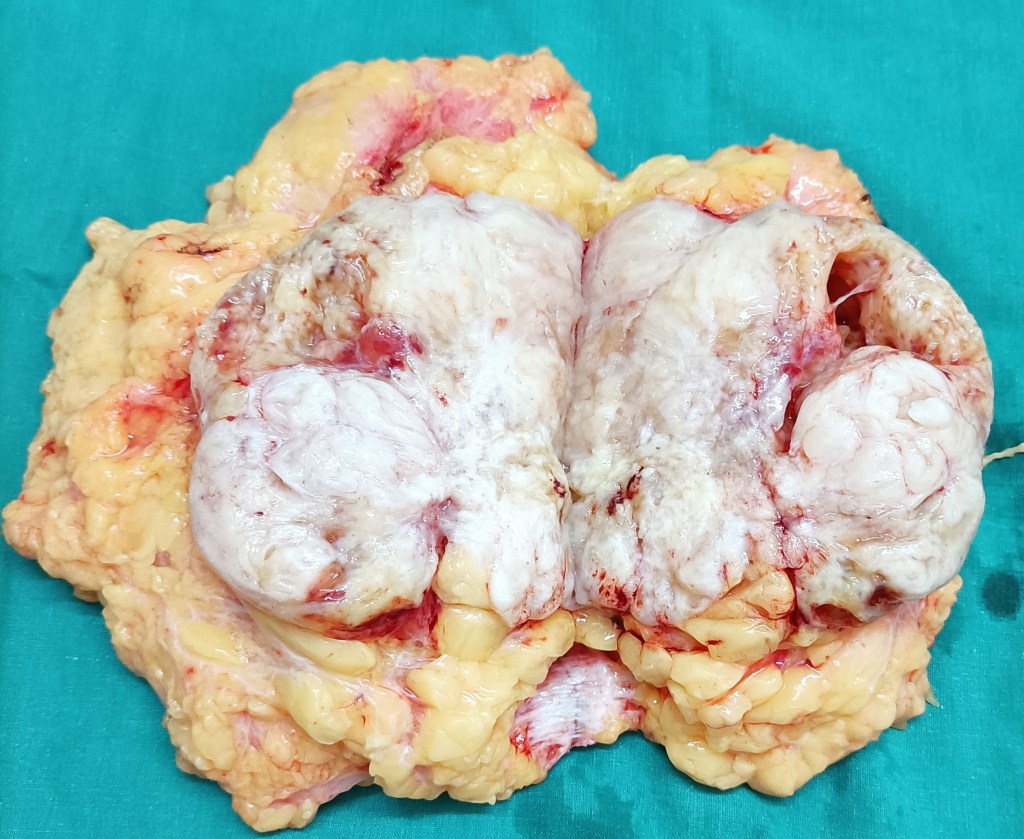

A big phyllodes tumor of the right breast removed at a simple total mastectomy (Dr Jagga’s case).